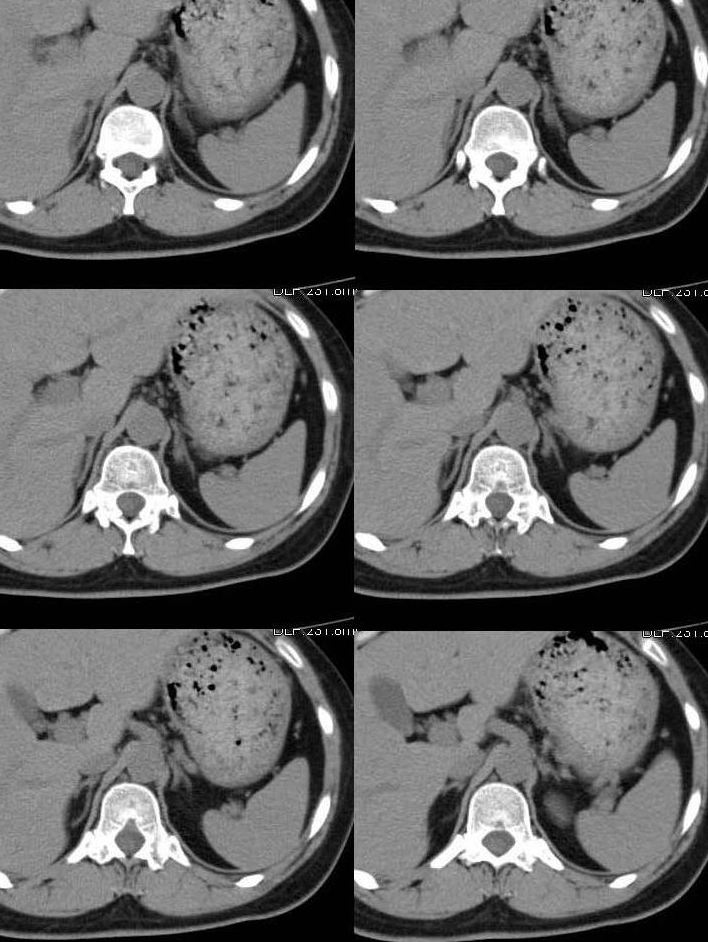

考虑左侧肾上腺内侧肢增粗(宽于同侧膈角最宽处)加上催产素异常增高,考虑左侧肾上腺增生

左侧肾上腺外侧支较同层面膈肌增粗。

我觉得左肾上腺内、外支都是增粗了

考虑左侧肾上腺内侧肢增粗(宽于同侧膈角最宽处)加上去甲异常增高,可符合左侧肾上腺增生.

左肾上腺内、外支都是增粗了,建议结合临床。

支持楼主:左侧肾上腺内侧肢相对增粗,并似有一结节影。去甲肾上腺素升高。考虑左侧肾上腺增生。